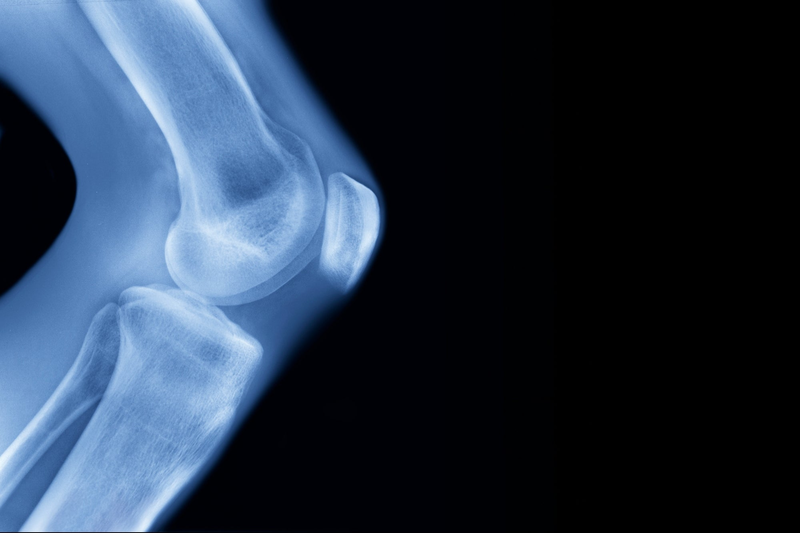

The doctor developed a method to implant and subsequently extend pins in the femur to increase height.

The doctor developed a method to implant and subsequently extend pins in the femur to increase height.